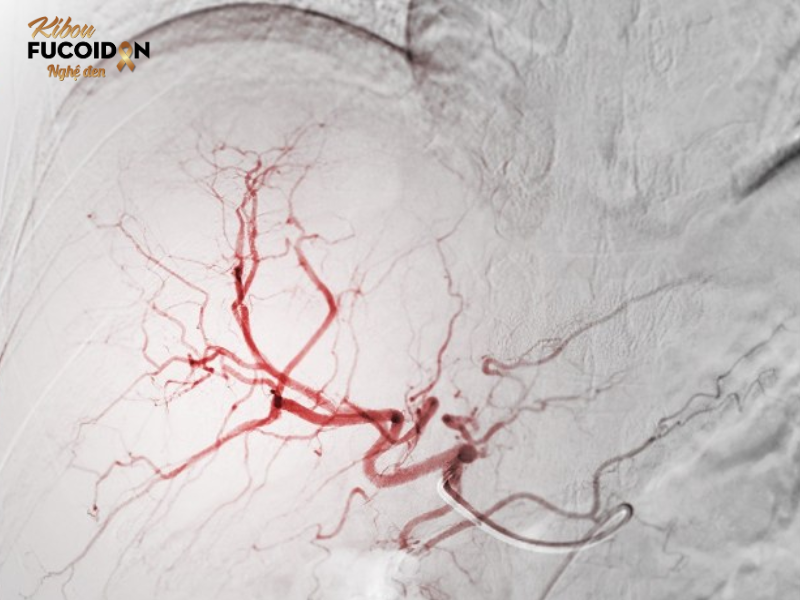

Giai đoạn trung gian: Nút mạch hóa chất (TACE) để “bỏ đói” khối u.